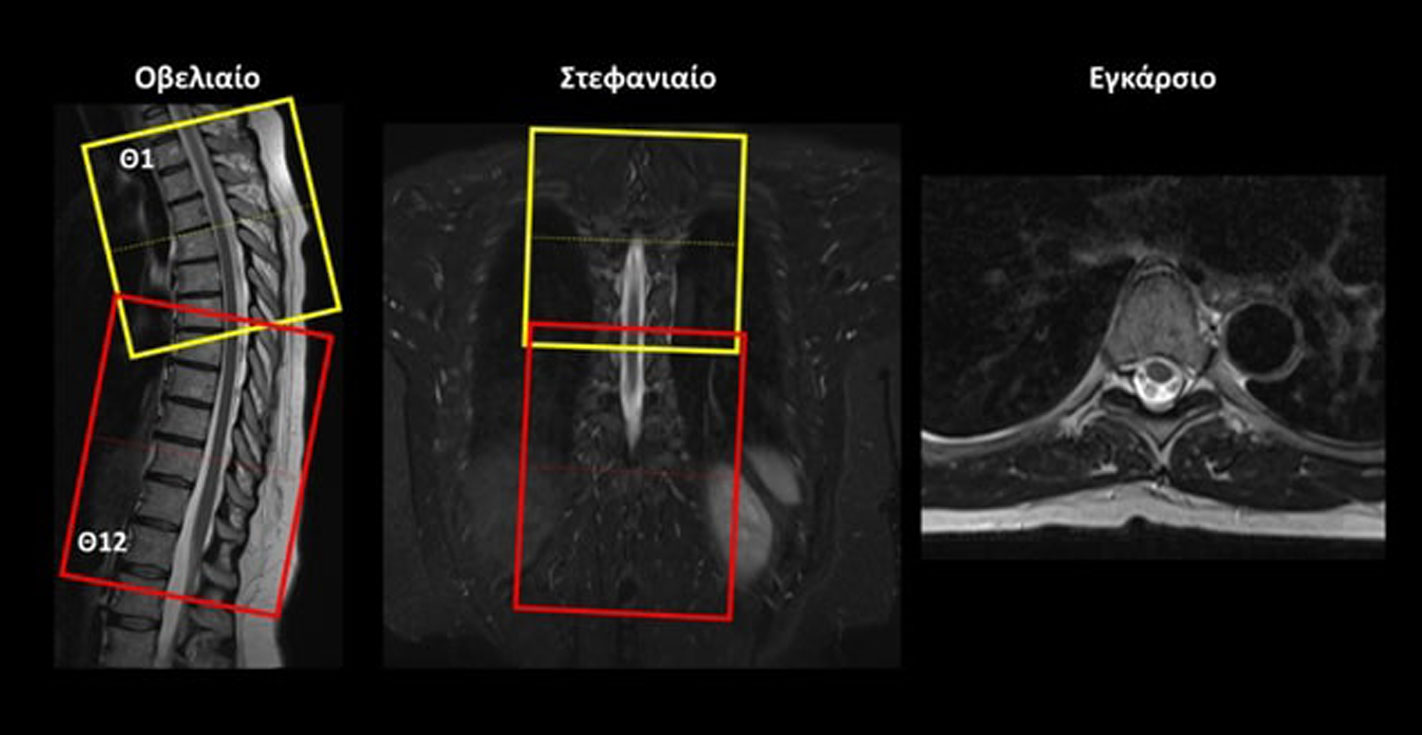

Οβελιαίο (Sagittal): οι οβελιαίες τομές σχεδιάζονται παράλληλα με τον νωτιαίο μυελό στο στεφανιαίο επίπεδο. Οι τομές περιλαμβάνουν μόνο τον νωτιαίο μυελό, από τα δεξιά έως τα αριστερά.

Εγκάρσιο (Axial/Transversal) στην ΑΜΣΣ: οι εγκάρσιες τομές σχεδιάζονται κάθετα στον νωτιαίο μυελό, τόσο στο οβελιαίο όσο και στο στεφανιαίο επίπεδο. Οι τομές πρέπει να περιλαμβάνουν ολόκληρο τον αυχενικό νωτιαίο μυελό, από το ινιακό τρήμα έως το επίπεδο Α7-Θ1.

Εγκάρσιο (Axial/Transversal) στην ΘΜΣΣ: λαμβάνονται 2 επικαλυπτόμενα πακέτα, και οι εγκάρσιες τομές σχεδιάζονται κάθετα στον νωτιαίο μυελό, τόσο στο οβελιαίο όσο και στο στεφανιαίο επίπεδο. ΠΡΟΣΟΧΗ! Τα δυο πακέτα πρέπει να ληφθούν ως δύο διαφορετικές ακολουθίες ώστε να μην δημιουργηθεί τεχνικό σφάλμα διασταυρούμενης διέγερσης (cross-talk) στο επίπεδο που τέμνονται οι τομές. Οι τομές πρέπει να περιλαμβάνουν από το επίπεδο Α7-Θ1 έως και το επίπεδο Ο1-Ο2, με σκοπό η κάλυψη να περιλαμβάνει έως και τον μυελικό κώνο.